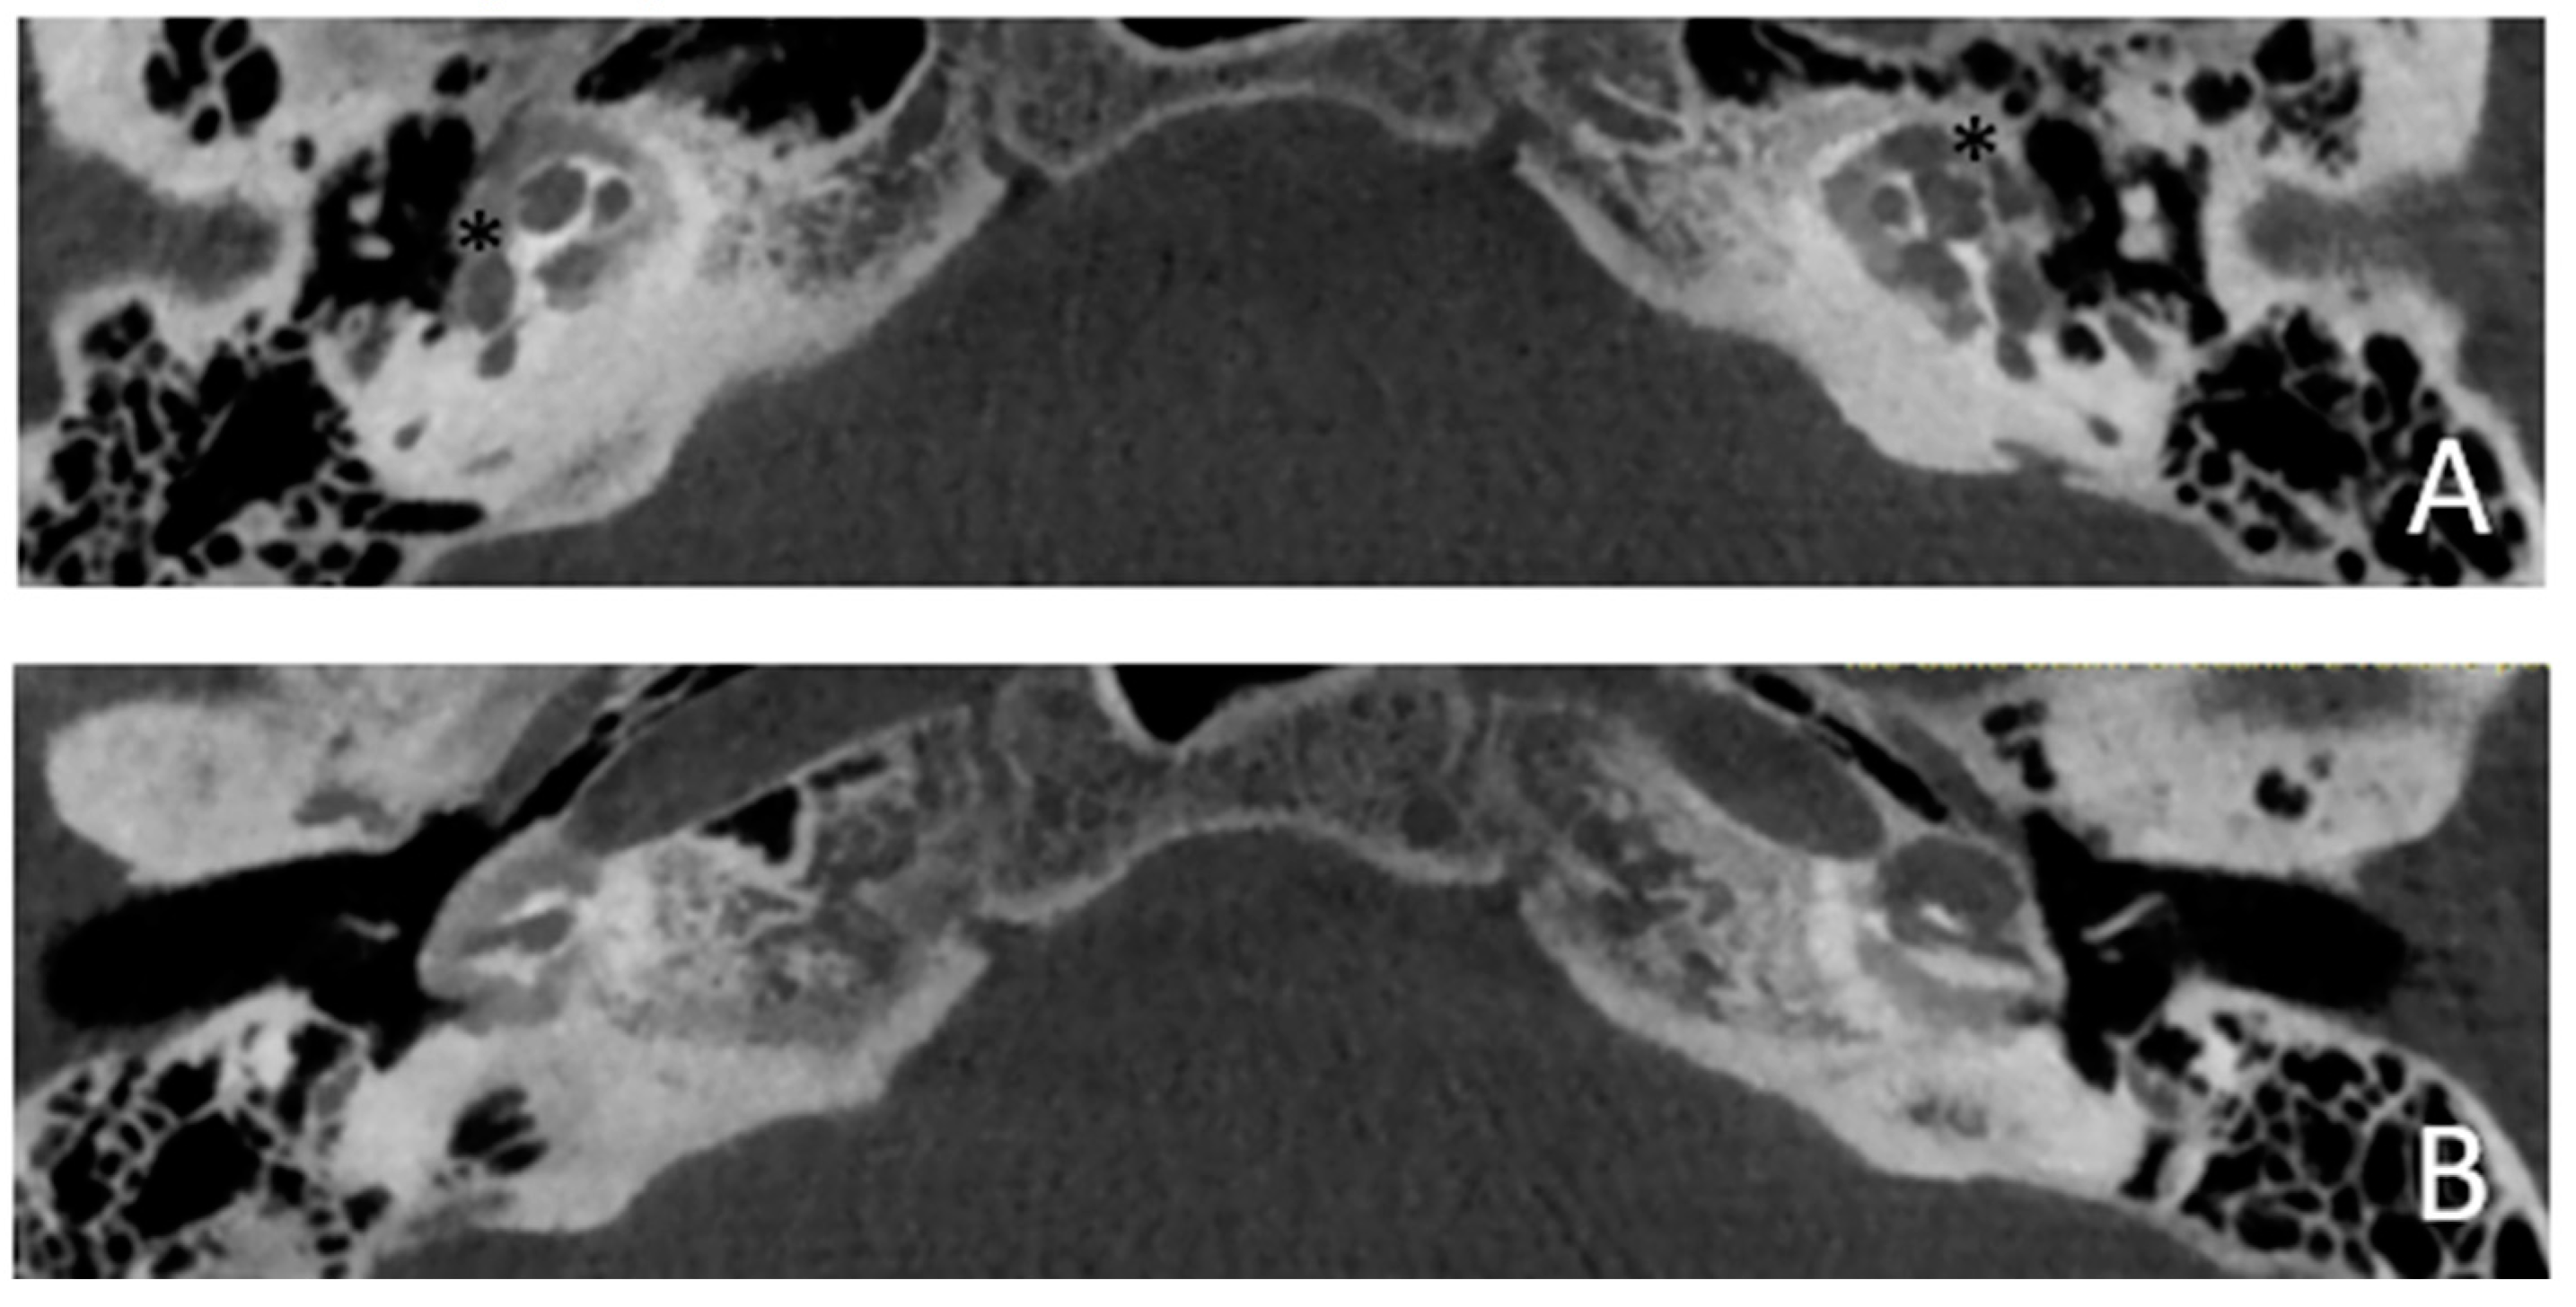

Patient #4, affected by otosclerosis: He developed mild SNHL since the age of 30 and in a few years (12 years) he had a severe progression to anacusis. The patient underwent right cochlear implantation with excellent results. CT and MR images show a large empty space communicating with the cochlea bilaterally (Figure 7 and Figure 8).

Figure 7. CT images of patient #4 with otosclerosis. A and B, axial plane. The cavity around the cochlea is clearly visible as well as the communication of the cavitating osteorarefation with the cochlea,marked with asterisks.

Figure 8. MR images of patient #4 with otosclerosis. MR cisternography, axial plane. Note the fluid signal in the newly formed cavity (white asterisks).